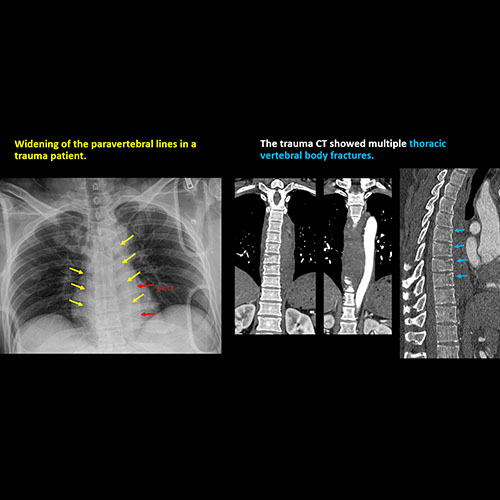

The prevertebral or paravertebral soft tissues are abnormal. |

Yes | NA |

There is an oblique fracture with avulsion through the anterior inferior T9 vertebral body. The posterior elements are intact. There is excessive calcification of the anterior longitudinal ligament and there are continuous osteophytes in a pattern consistent with DISH (Diffuse Idiopathic Skeletal Hyperostosis).

The findings were called to the referring physician and a CT scan is planned.